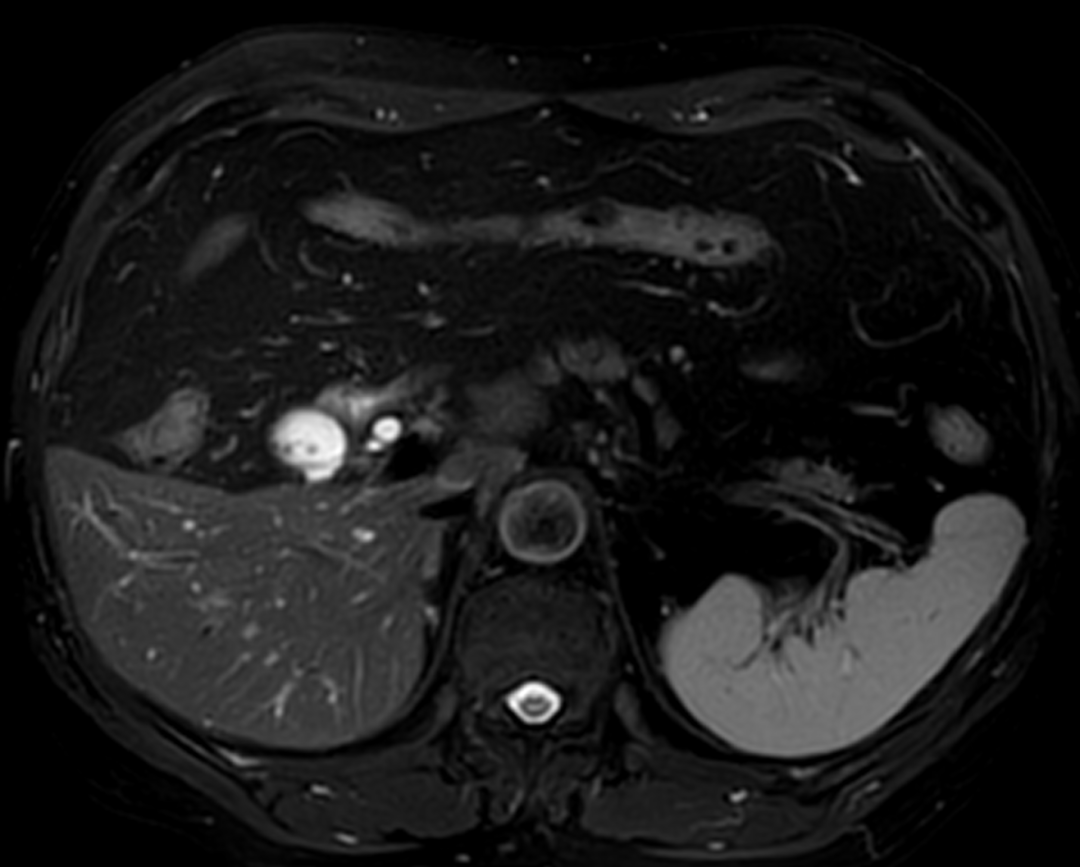

考虑到王老先生高龄加上心血管系统基础疾病,术前普外医师团队和麻醉团队进行了详尽准备。在术前影像学检查的精准导航下,段琨副主任医师带领手术团队,凭借精湛的腹腔镜技术和丰富的临床经验,精细解剖胆囊三角区,完整切除病变胆囊,仔细止血胆囊床,探查确认胆总管无损伤,手术过程顺利,术后患者生命体征平稳。因腹腔镜手术创伤小、术中出血少、术后疼痛轻、恢复快、疤痕小等优点,王老先生第二天即可下床活动,第三天腹腔引流管拔除,经过一周的精心治疗及护理顺利出院。王老先生表示,“在手术室,麻醉科李虎主任认真负责风趣幽默,缓解我的紧张情绪,让我在手术台上放松下来。手术体验也比预想好得多,术后几乎无明显不适。”